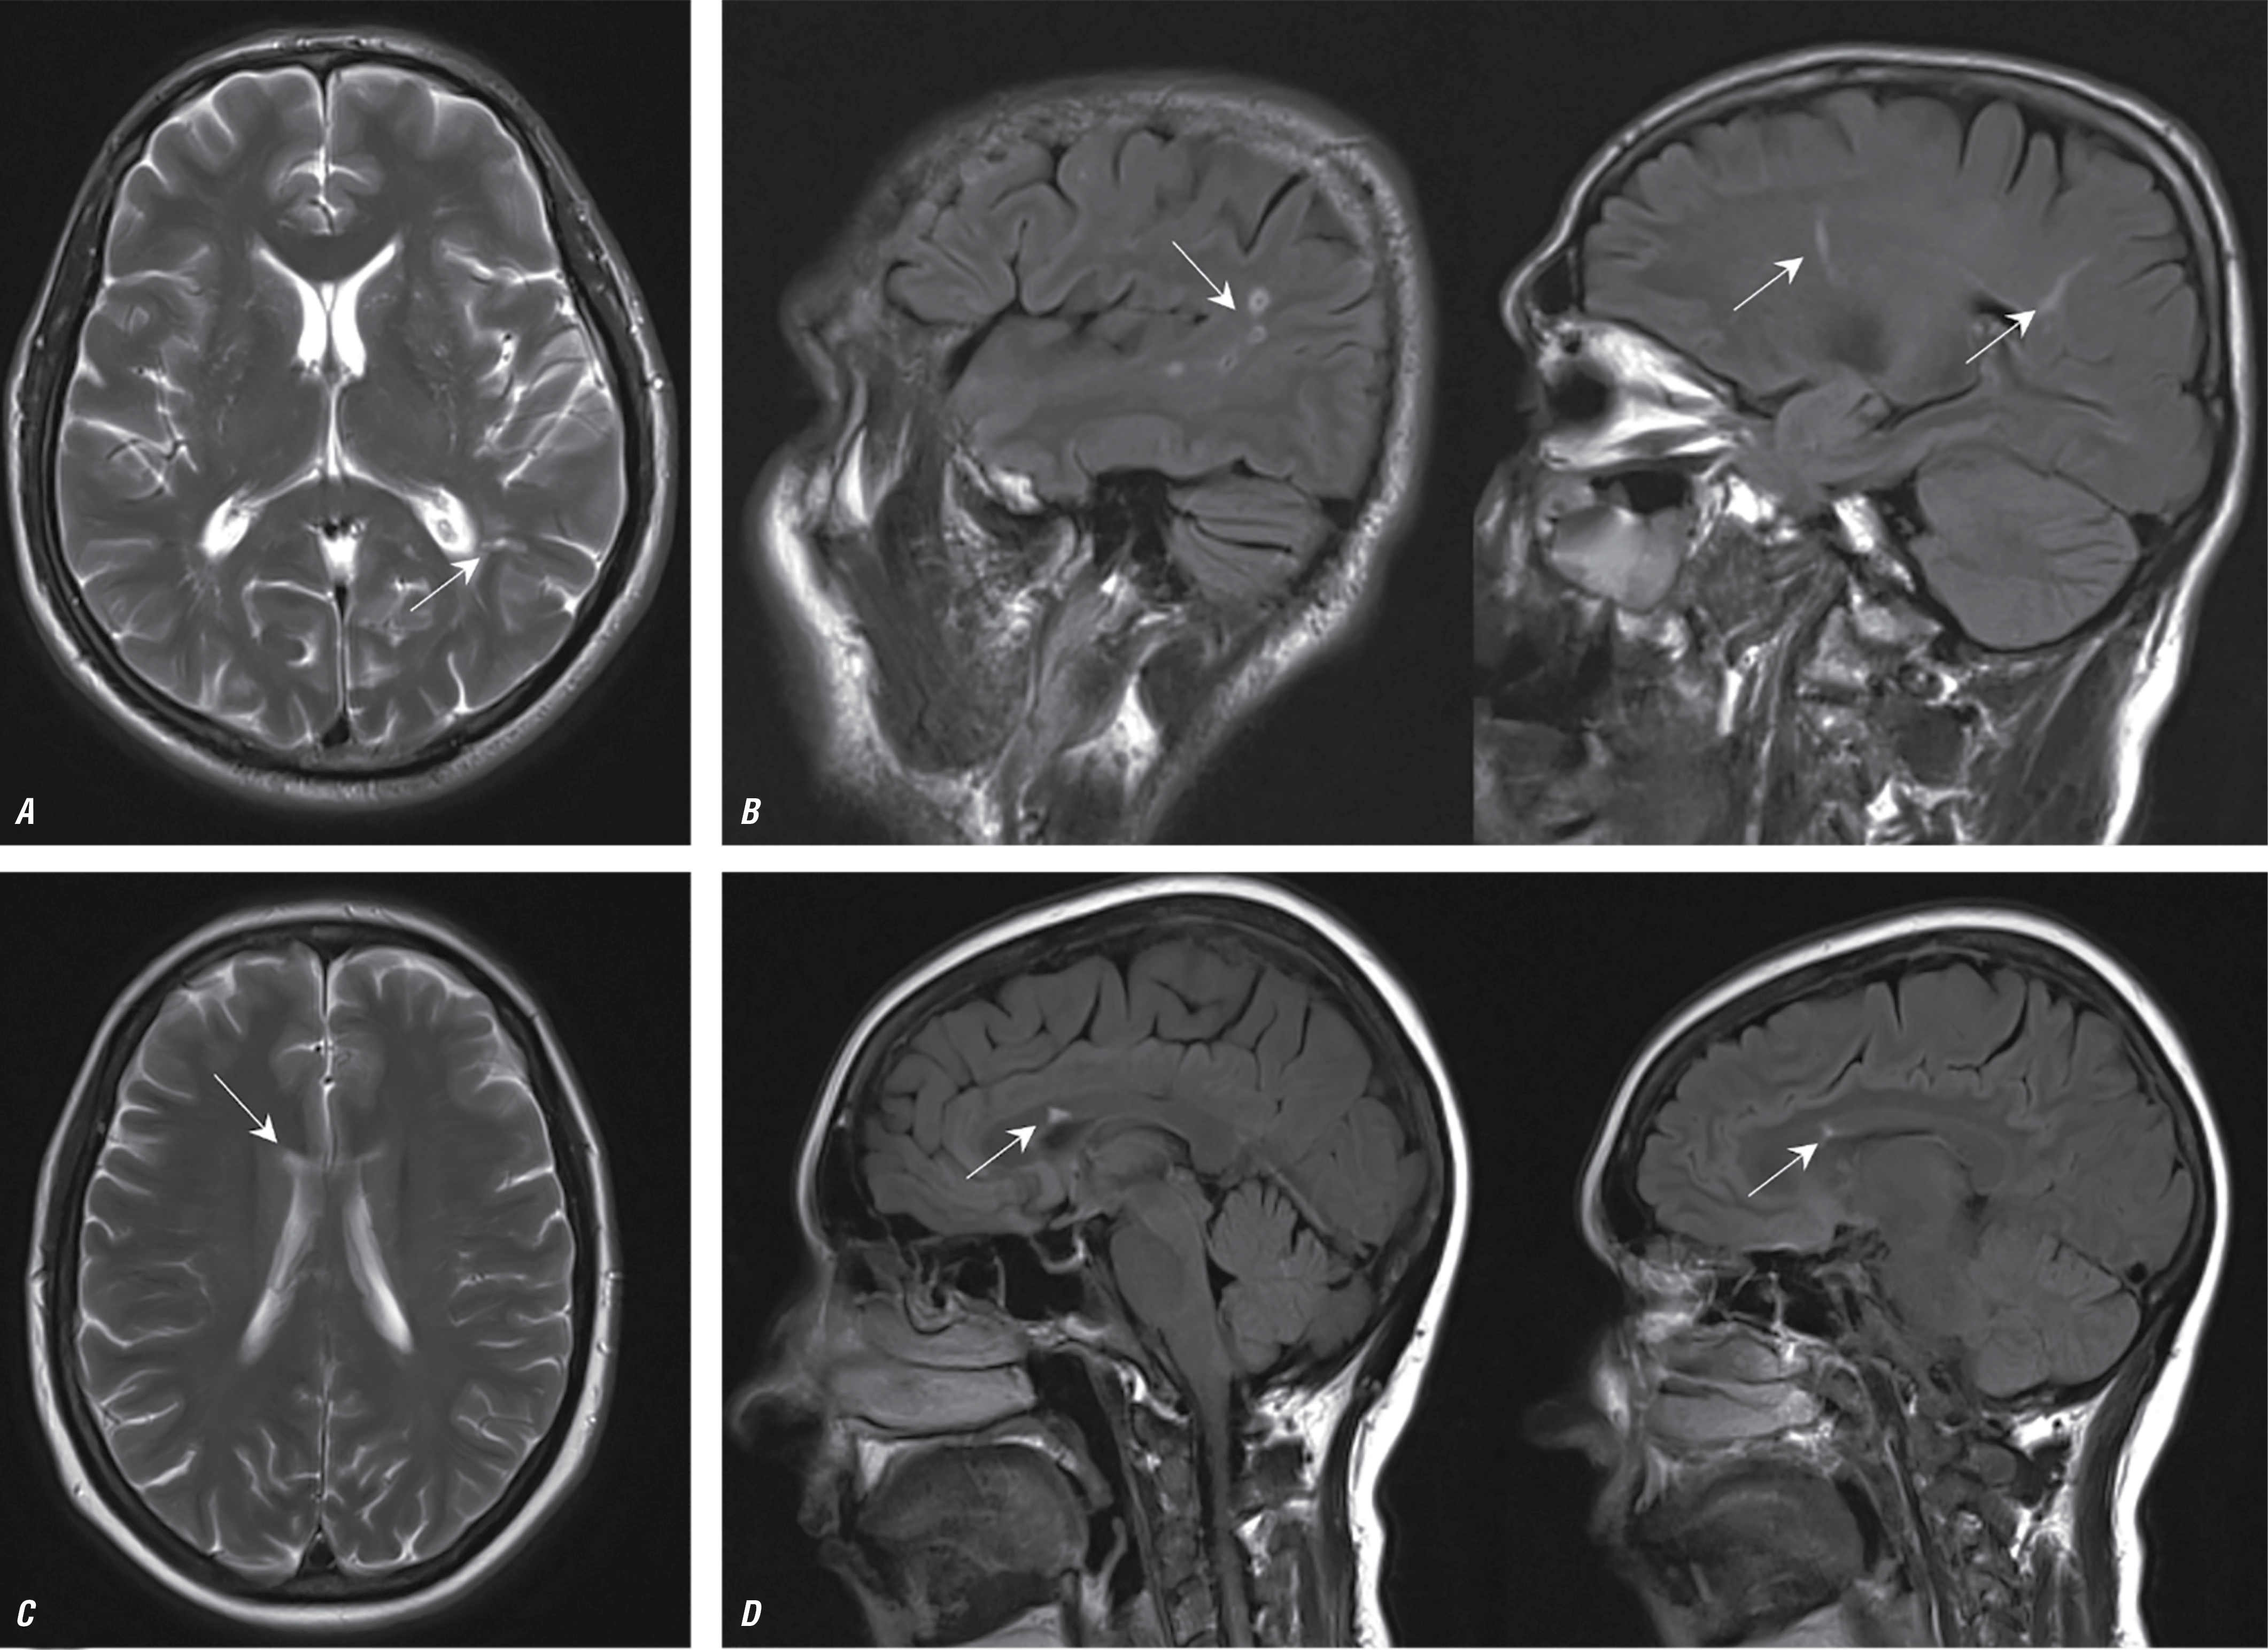

Рис. 4. МРТ головного мозга пациентов с ЭТ — Т2-взвешенные изображения в аксиальной плоскости.

Во всех случаях визуализируются массивные постинфарктные изменения с вовлечением коры, подлежащего и глубокого белого вещества, а также базальных ганглиев (постинфарктные изменения указаны стрелками).

Fig. 4. Brain MRI of patients with ET; axial plane T2-weighted images.

In all cases, massive post-infarction changes are found in the cortex, underlying and deep white matter, and basal ganglia (post-infarction changes are indicated by arrows).

Эссенциальная тромбоцитемия

Характерными нейровизуализационными признаками НМК при ЭТ являлись массивные постинфарктные изменения с вовлечением коры, подлежащего и глубокого белого вещества, базальных ганглиев с частотой встречаемости 67%. В 26% случаев НМК развивалось на фоне тромботической окклюзии внутренней сонной артерии с последующим формированием массивного очага ишемии в веществе мозга. В большинстве случаев клиническая картина была представлена острым началом с развитием грубого неврологического дефицита. В 26% случаев постинфарктные изменения в веществе головного мозга встречались в бассейне вертебрально-базилярной системы, в 74% — в каротидном бассейне. В 33% случаев последствия НМК привели к развитию стойкой утраты дееспособности и инвалидности (средний возраст пациентов — 32 года).

Ведущим нейровизуализационным паттерном последствий НМК при ЭТ был большой объём поражения вещества мозга с корково-подкорковой локализацией (рис. 4).